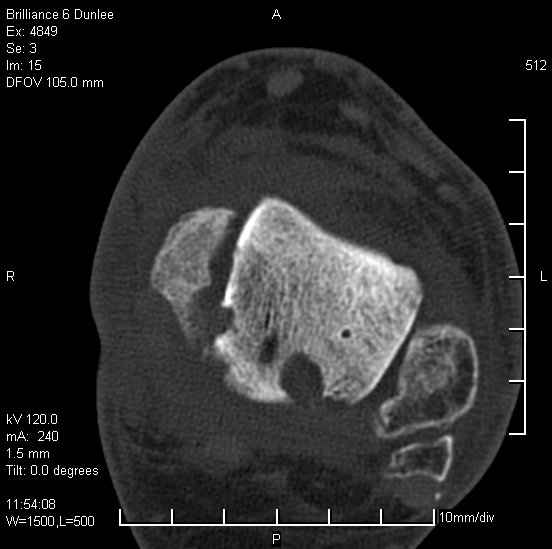

На лечении находится пациент 35 лет. Травма в сентябре 2008 г.- открытый вывих таранной кости

В день травмы ПХО, вправление вывиха, трансартикулярная фиксация. Рана зажила первично. С января нагрузка на конечность. С конца апреля- болевой синдром. На рентгенограммах и КТ признаки ас. некроза таранной кости, артроз подтаранного и голеностопного суставов.